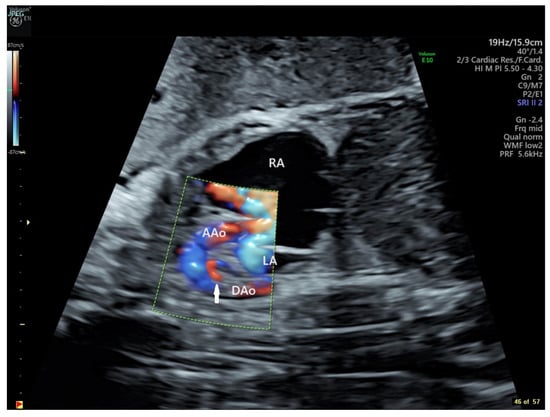

Fetal echocardiography was consistent with a diagnosis of Ebstein anomaly with severe tricuspid regurgitation and right atrial (RA) dilation, large tricuspid annulus dimension (Z score +3.5), right ventricular (RV) enlargement (diameter Z score +3.7), mild pulmonary annulus hypoplasia (Z score −2.7), pulmonary insufficiency with retrograde flow in a reverse-oriented ductus arteriosus, and normal branch pulmonary arteries (Figure 1). Tricuspid regurgitation jet velocity was low at 2.3 m/s [1,10,11], consistent with decreased right ventricular performance. At the time of consultation, the fetus was in a virtually incessant supraventricular tachycardia (long RP) with a rate of 203 bpm alternating with several beat runs of sinus vs. atrial rhythm with rates of 150–171 bpm. There was no evidence of fetal hydrops.

Figure 1. Panel (A): Paired fetal echocardiographic apical still frame images showing cardiomegaly, right atrial dilation, tricuspid annular dilation, and right ventricular enlargement at presentation at 28 6/7 weeks gestation. RA = Right Atrium, RV = Right Ventricle, LA = Left Atrium, LV = Left Ventricle. Doppler Color flow mapping superimposed on the panel at right demonstrates severe tricuspid insufficiency (arrow). Panel (B): Paired fetal echocardiographic sagittal still frame images of the dilated RV, the normal-sized RVOT, and the reverse-oriented ductus. RV = Right Ventricle, PV = Pulmonary Valve, MPA = Main Pulmonary Artery, LV = Left Ventricle, DA = Ductus Arteriosus. Doppler Color flow mapping in the panel at right demonstrates retrograde flow in the reverse-oriented ductus (blue), retrograde flow in the main pulmonary artery (orange), and marked pulmonary valve insufficiency (red). All images were produced on a GE Voluson E10 Ultrasound System.